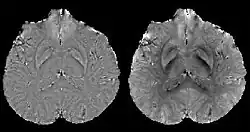

COSMOS assumes a model-free susceptibility distribution and keeps full fidelity to the measured data. This method has been validated extensively in in vitro, ex vivo and phantom experiments. Quantitative susceptibility maps obtained from in vivo human brain imaging also showed high degree of agreement with previous knowledge about brain anatomy. Three orientations are generally required for COSMOS, limiting the practicality for clinical applications. However, it may serve as a reference standard when available for calibrating other techniques.

MEDI has also been validated extensively in phantom, in vitro and ex vivo experiments. In an in vivo human brain, MEDI calculated QSM showed similar results compared to COSMOS without statistically significant difference.[15] MEDI only requires a single angle acquisition, so it is a more practical solution to QSM.